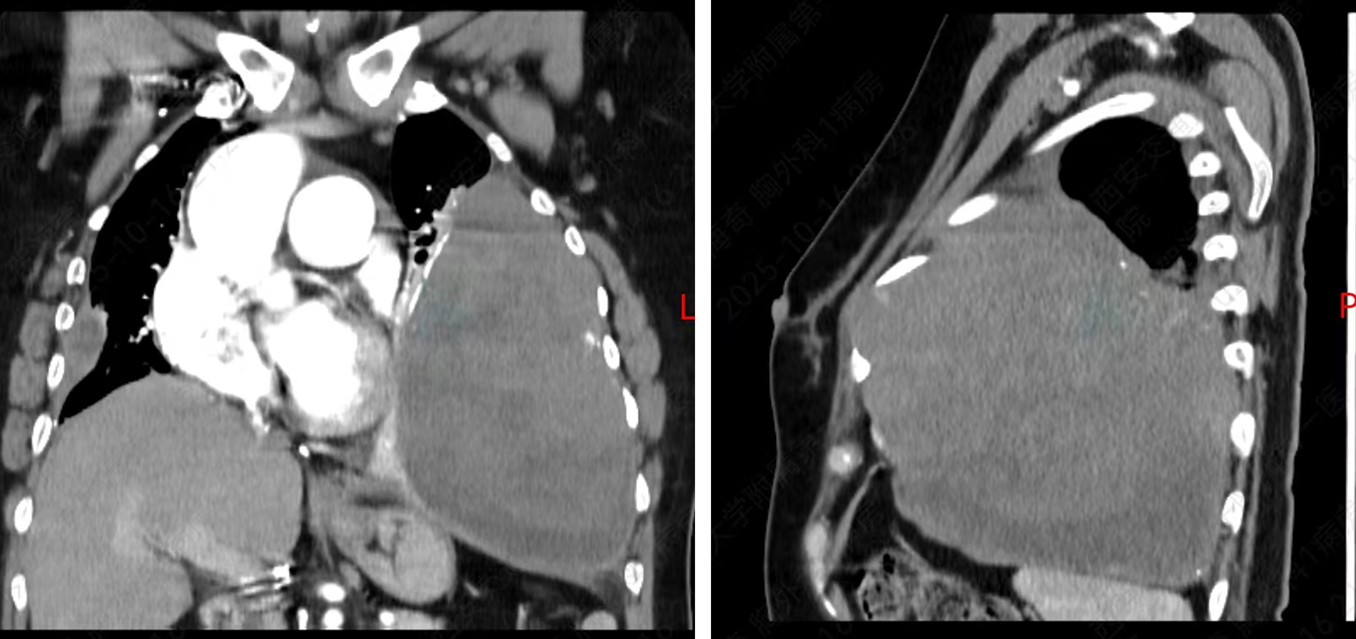

抱着一线希望,李女士来到西安交大一附院陆港院区胸外科。科室迅速组织全面评估,CT显示肿物已达18cm×15cm,占据左侧胸腔大部分空间,压迫心脏移位,使其向右侧偏移。

主治医师贺海奇介绍:“肿瘤虽考虑为良性或低度恶性,但体积巨大,术中出血风险非常高,对团队是极大考验。”面对挑战,胸外科张广健主任带领团队反复研究影像资料,模拟手术路径,制定周密手术方案及应急预案,全力为患者争取生机。

图1 术前CT检查显示肿瘤最大径超过18cm